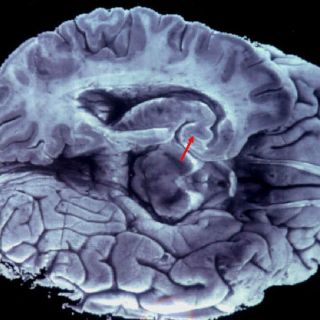

CIUDAD DE MÉXICO (07/DIC/2015).- Un médico mexicano mejoró un neuroestimulador, que diseñó en 2001, para mejorar las terapias de electroestimulación en tratamientos contra la

migraña y de diversas enfermedades oculares, informó la Agencia Informativa del

Conacyt.